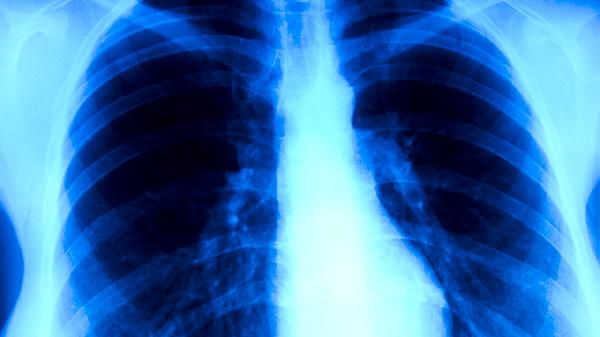

肺结核患者即使症状消失也不应自行停药,痰菌转阴后仍需巩固治疗。标准短程化疗方案通常需要6-9个月,分为强化期和巩固期两个阶段。强化期使用异烟肼片、利福平胶囊、吡嗪酰胺片、乙胺丁醇片四种药物联合治疗,巩固期减少为异烟肼片和利福平胶囊两种药物。治疗期间需定期复查胸部X线、痰涂片及肝肾功能,医生会根据病灶吸收程度、细菌学检查结果调整用药方案。完成全程治疗后,还需进行1-2年随访观察。